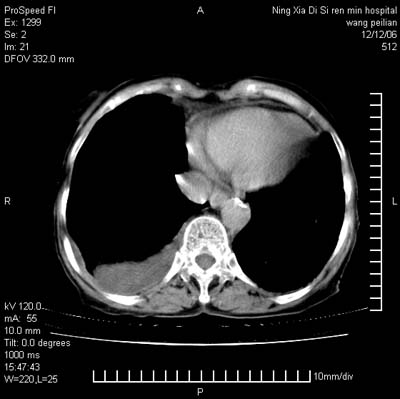

标题: CT5609:胸部:女77 病史不详 [打印本页]

标题: CT5609:胸部:女77 病史不详

两肺尖纤维索状影,两下肺结节块状影,且有钙化灶,右胸腔积液。考虑肺结核并胸膜炎。

双侧肺结核伴右侧胸腔积液.

两肺以间质性病变为主,并有胸腔积液,考虑结核

考虑:1、慢性支气管炎合并全小叶型肺气肿、间质纤维化;

2、双肺结核;

3、右侧胸膜炎(积液)。